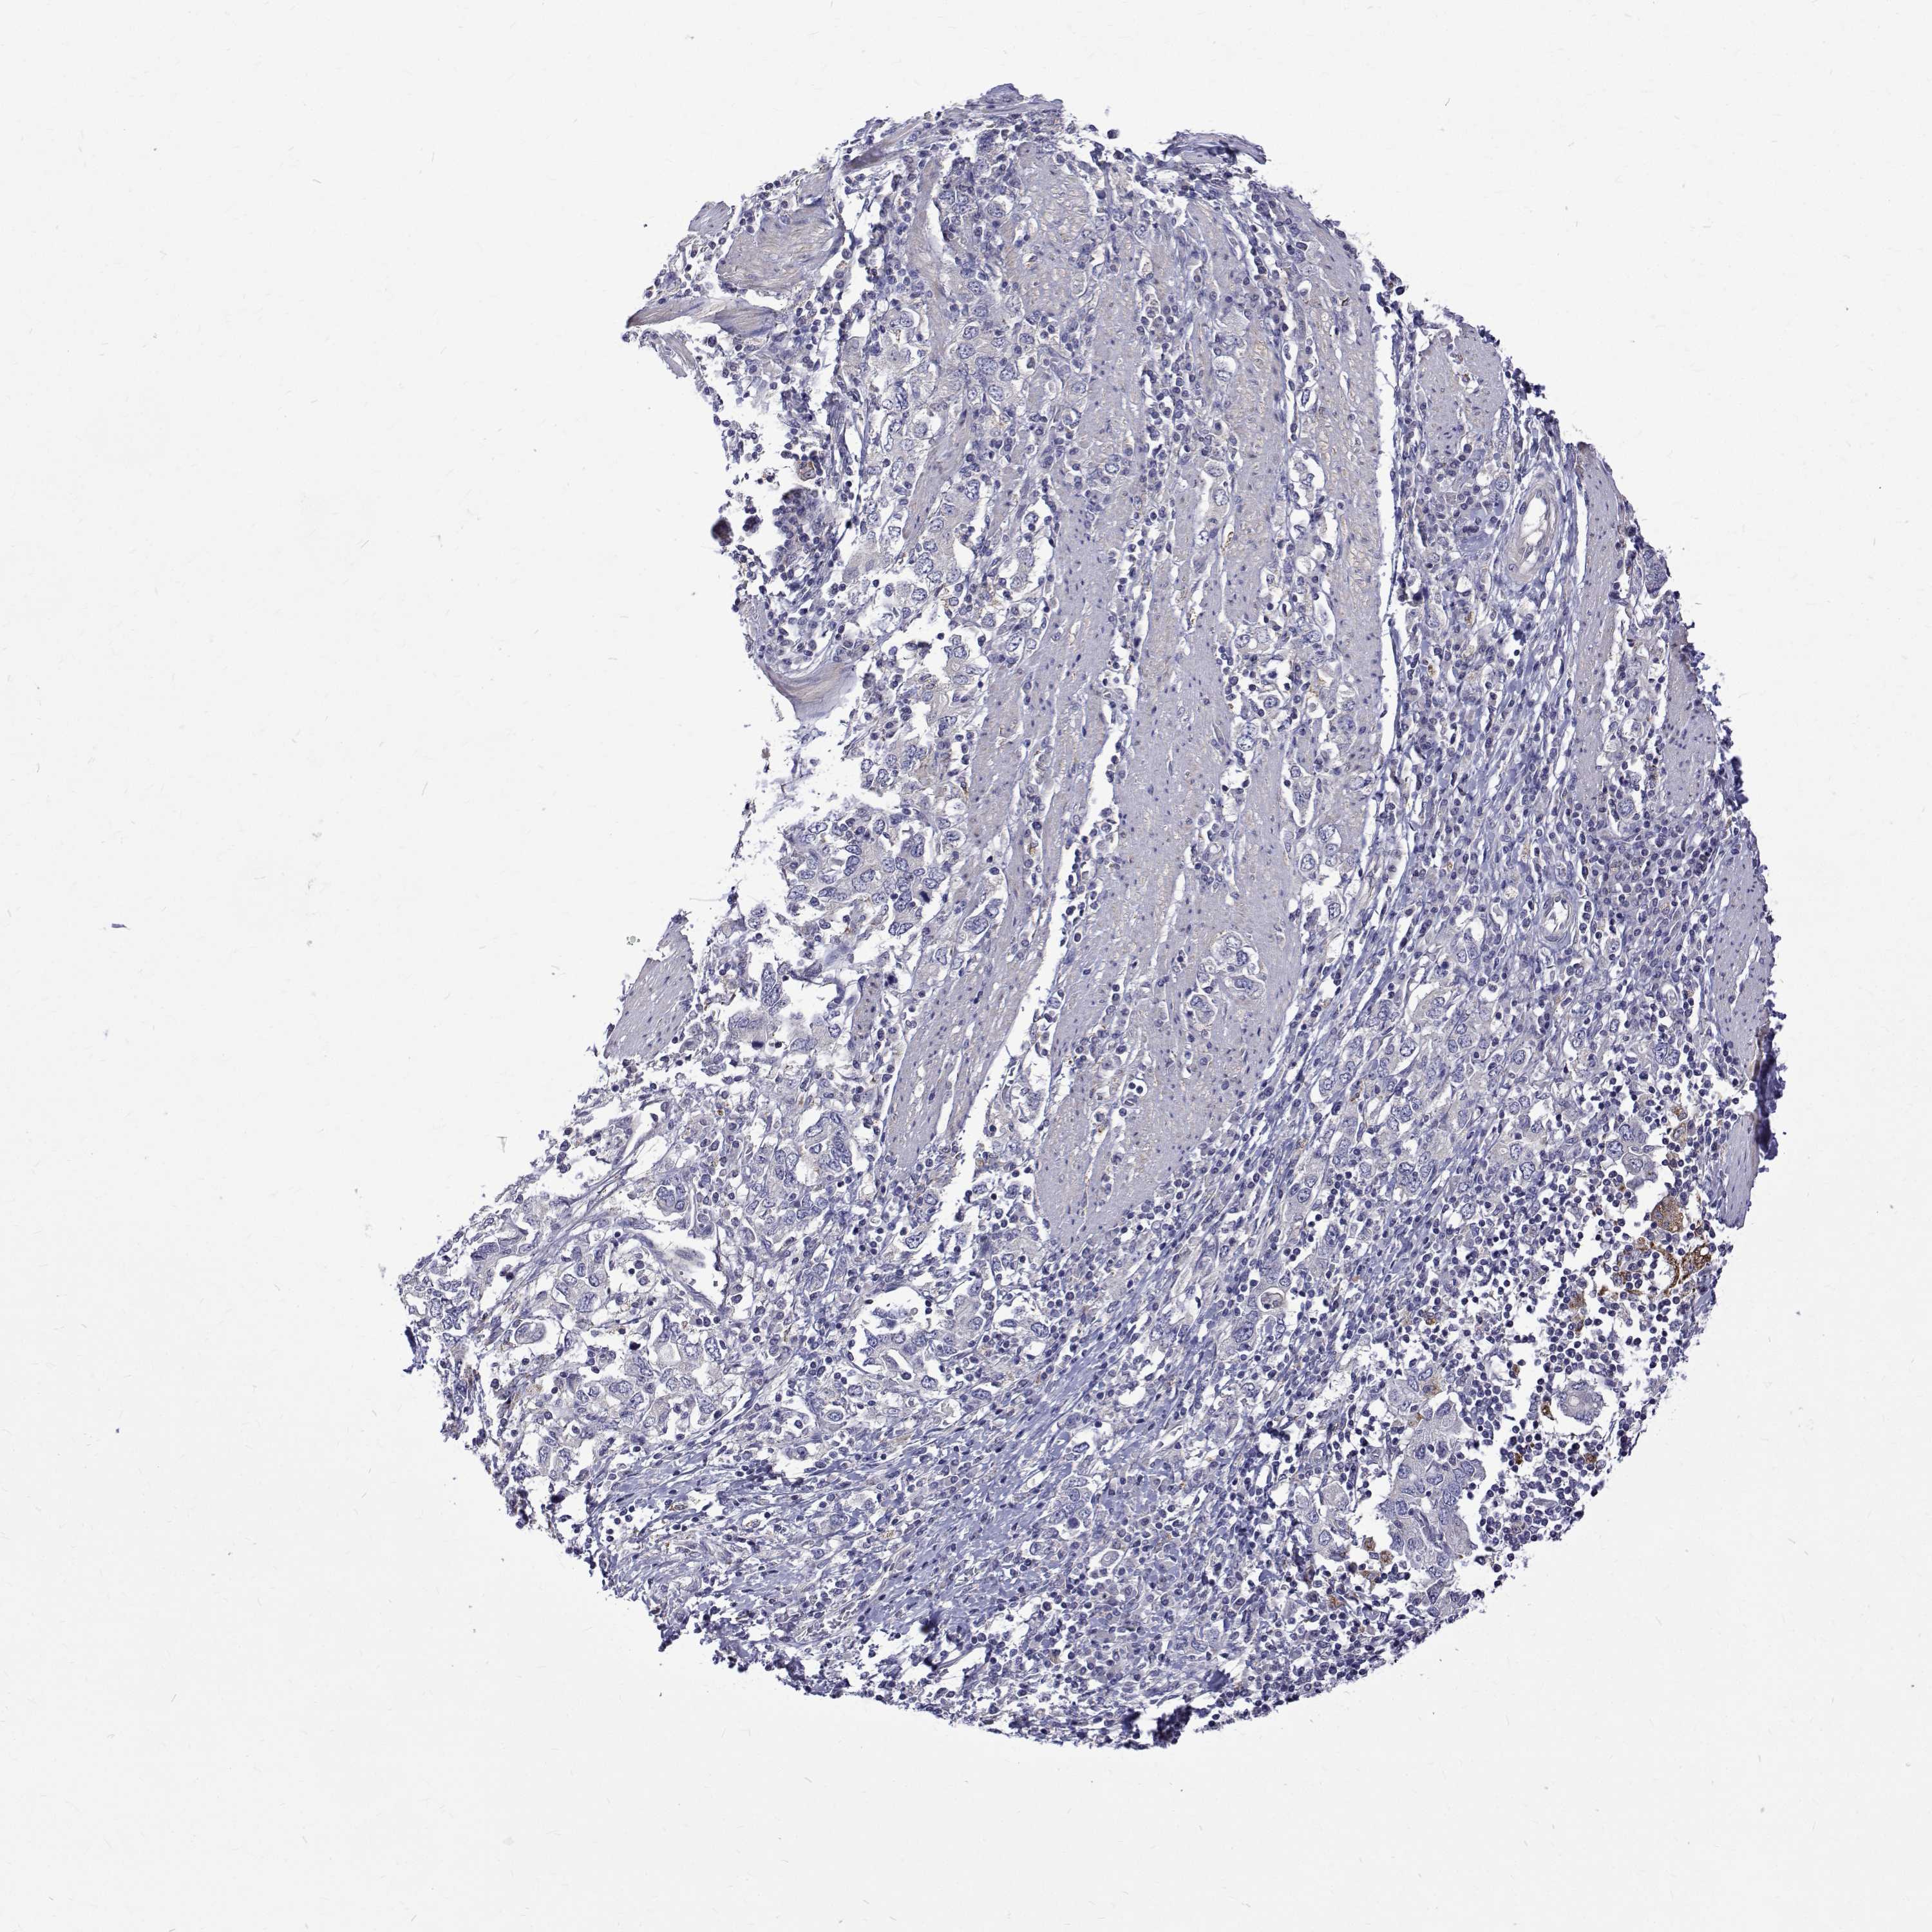

STOMACH CANCER - Protein expressioni

A mouse-over function shows sample information and annotation data. Click on an image to view it in a full screen mode. Samples can be filtered based on level of antibody staining by selecting one or several of the following categories: high, medium, low and not detected. The assay and annotation is described here.

Note that samples used for immunohistochemistry by the Human Protein Atlas do not correspond to samples in the TCGA dataset.

Antibody stainingi

Antibody staining in the annotated cell types in the current human tissue is reported as not detected, low, medium, or high, based on conventional immunohistochemistry profiling in selected tissues. This score is based on the combination of the staining intensity and fraction of stained cells.

Each image is clickable and will lead to virtual microscopy that enables deeper exploration of all samples and also displays staining intensity scores, fraction scores and subcellular localization as well as patient and tissue information for each sample.

Antibody HPA062294

Staining

High

Medium

Low

Not detected

Intensity

Strong

Moderate

Weak

Negative

Quantity

>75%

75%-25%

<25%

None

Location

Nuclear

Cytoplasmic/membranous

Cytoplasmic/membranous,nuclear

Adenocarcinoma, NOS